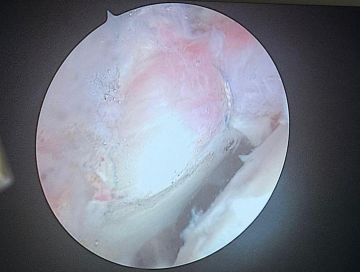

نجح الفريق الطبي في قسم جراحة العظام بمستشفى الملك فهد عضو تجمع المدينة المنورة الصحي من إجراء عملية خياطة لغضروف مفصل الورك باستخدام المنظار لمستفيدة، وذلك ضمن التوجه المتقدم نحو تبنّي أحدث التقنيات الجراحية في مجال جراحة المفاصل والطب الرياضي.

وأوضح تجمع المدينة المنورة الصحي أن المستفيدة حضرت إلى العيادات وهي تعاني من آلام مزمنة في مفصل الورك مع صعوبة في الحركة نتيجة تمزّق في الغضروف الحُقّي (Labrum)، وبعد استكمال الفحوصات السريرية والتصويرية، تقرّر إجراء العملية بالمنظار كخيار متقدّم يوفّر دقة أعلى وأضراراً أقل على الأنسجة مقارنة بالجراحات التقليدية.

وأضاف التجمع أن العملية أُجريت من خلال فتحات صغيرة، تم عبرها الوصول للمفصل وإصلاح التمزّق باستخدام تقنيات خياطة متقدمة تُحافظ على الغضروف وتعيد وظائف المفصل الطبيعية، حتى تكللت الجراحة بالنجاح دون أي مضاعفات، وتمكّنت المستفيدة من البدء في برنامج التأهيل الحركي خلال الساعات الأولى بعد العملية.

ويُعد هذا الإجراء خطوة هامة في تطوير خدمات جراحة الورك والمناظير المتقدمة في المنطقة، ويفتح المجال لتقديم حلول علاجية دقيقة كانت تحتاج لتدخلات جراحية أكبر.